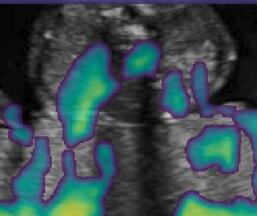

Fig. 6 compares the shadow confidence maps of the state-of-the-art methods and the proposed methods. RW and have the same parameters as used for Table I. The shadow confidence maps of the baseline, the proposed method and the proposedAG method are generated directly from input shadow images by confidence estimation networks. Overall, the proposed method and the proposedAG method achieve more visually reasonable shadow confidence estimation than the baseline and the state-of-the-art on different anatomical structures shown in Fig. 6. The proposed method and the proposedAG method are able to highlight multiple shadow regions while the RW algorithm shows limitations for most cases, especially for disjoint shadow regions.

Row I in Fig. 6 shows a fetal brain image from . The confidence estimation of shadow regions from the baseline, the proposed method and the proposedAG method are similarly accurate since we use fetal brain images to train the confidence estimation networks in these three methods. These outperform [16] and [22]. Rows (II-IV) in Fig. 6 show shadow confidence maps of non-brain anatomy from , including lips, abdominal and cardiac. The baseline failed on unseen data during inference. However, the proposed methods are able to generate accurate shadow confidence maps because of the generalized shadow features obtained by the shadow-seg module. Furthermore, the “Lips” example shows that our method is capable of detecting weaker shadow regions that have not been annotated in manual segmentation. This indicates that the confidence estimation network has learned general properties of shadow regions.

-D Alternative Examples of Shadow Confidence Estimation

We show an alternative group of examples for the confidence estimation of shadow regions (shown in Fig. 14). These examples include fetal brain from , and cardiac, lips, kidney from . Similar to the Fig. 6 in the main paper, Fig. 14 shows that the baseline fails to handle unseen data while the proposed method and the proposedAG method are able to predict pixel-wise confidence of multiple shadow regions. These examples demonstrate that the shadow-seg module is able to generalize the shadow representation and transfer shadow representation from the shadow/shadow-free classification task to a confidence estimation task.